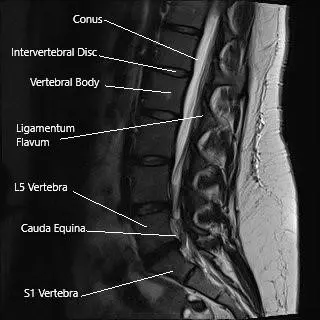

Sagittal section of the lumbosacral spine on MRI.

Sciatica is a myriad of symptoms caused by a pinched nerve in the back. The sciatic nerve is the largest nerve in the human body, starting from the back and dividing into various branches till the toes. The sciatic nerve is formed by the spinal nerves L4, L5, S1, S2, and S3.

In rare instances, the compression of nerve roots in the spinal canal may lead to cauda equina syndrome symptoms. Cauda equina syndrome involves weakness and numbness of lower extremities, numbness of the saddle area, and bowel and bladder control loss.

Radiological examinations for the hip usually include an X-Ray, which may or may not be followed by an MRI or a CT scan. The diagnosis of spinal pathologies causing sciatica usually requires an MRI investigation. An MRI is able to differentiate between the soft tissue structures such as nerves, ligaments, intervertebral disc, etc.